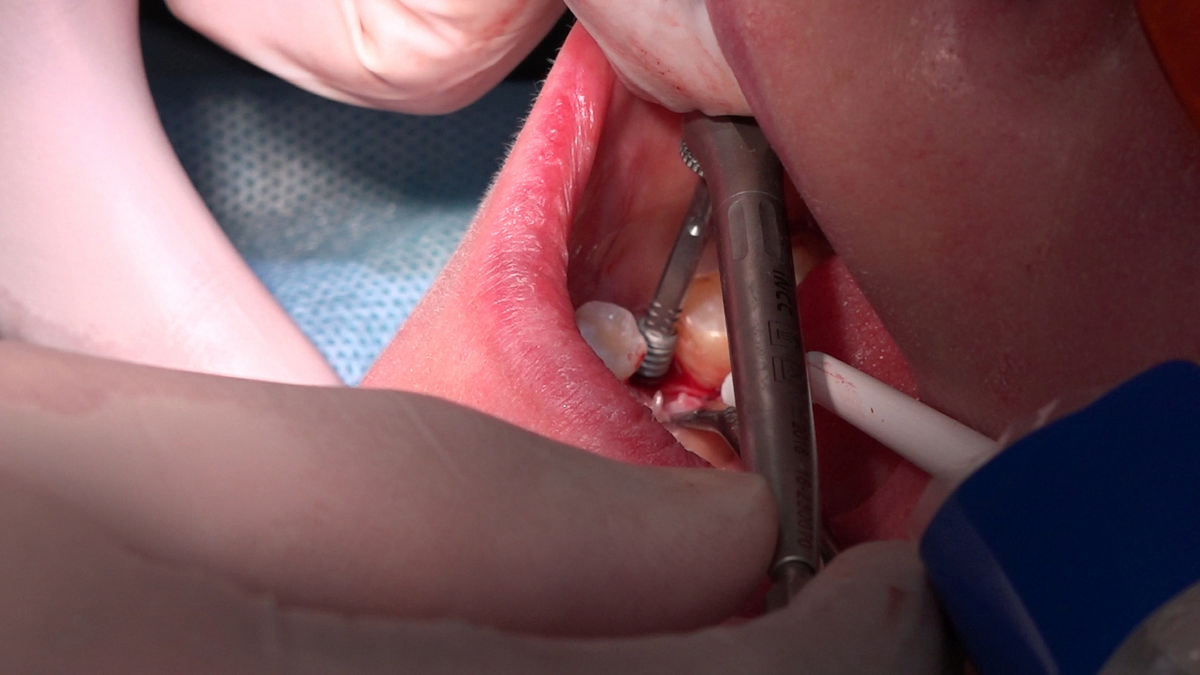

PRACTICULUM IMPLANTOLOGII - SEZON X - SESJA 4 - GRUPA B